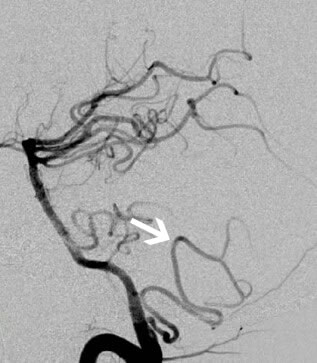

- სისხლძარღვოვანი ვიზუალიზაცია: გადამწყვეტია ძირითადი მიზეზის დასადგენად (ოკლუზია, სტენოზი, დისექცია) [4, 5].

- დსა (ციფრული სუბტრაქციული ანგიოგრაფია): რჩება ოქროს სტანდარტად სისხლძარღვების დეტალური ანატომიისთვის, განსაკუთრებით დისტალური სისხლძარღვებისთვის, დისექციის ფლეპებისთვის ან მცირე დაზიანებებისთვის, მაგრამ არის ინვაზიური და გამოიყენება სპეციფიკური ჩვენებების დროს ან როდესაც განიხილება ენდოვასკულური მკურნალობა.